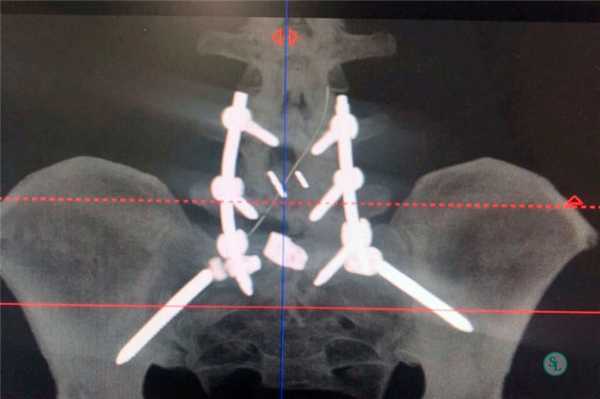

Транспедикулярная фиксация или ТПФ - операция, при которой позвонки фиксируются и стабилизируются при помощи специальных имплантов (транспедикулярных винтов). В каждом позвонке есть точка ввода винта, которую установил в 1985 году Рой Камилл — это точка пересечения поперечного отростка позвонка с верхнем суставным отростком. С помощью специальных инструментов в эту точку, вкручиваются винты определяя анатомически правильное расположение позвоночника, тем самым излечивая заболевание. Первые попытки установки имплантов были в 60-70 гг. прошлого века и с тех пор является «золотым стандартом» в лечения переломов и различных заболеваний позвоночника.

ТПФ выполняется под рентгеновским контролем, что позволяет хирургу точно контролировать каждое движение и избежать повреждения близкорасположенных анатомических структур. Чаще для этого используется ЭОП или КТ.

Очень важно при установки винтов соблюсти следующие моменты: отсутствие пространства между костью и винтом, исключение травматизации нервных и сосудистых структур или смежных дугоотросчатых суставов. Импланты устанавливаются согласно размерной линейки каждого позвонка и винта, бикортикально не касаясь замыкательных пластин.

Точка установки винта в корень дуги подбирается на основании расположения двух анатомических ориентиров - поперечного и суставного отростков позвонка. Непосредственно позвонок перфорируют с помощью специального зонда.